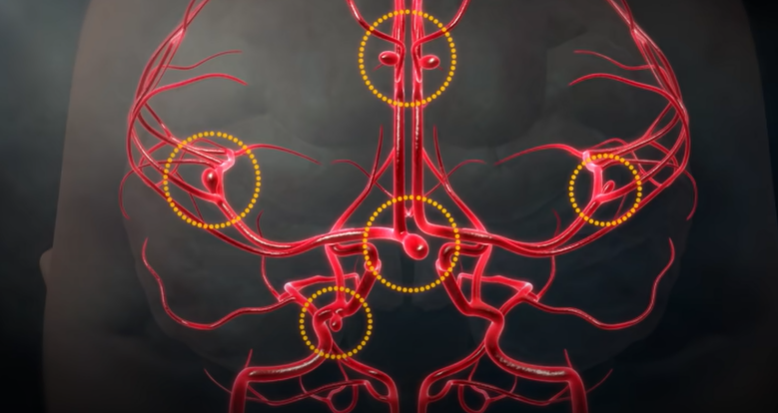

아래 사진의 특정 환자의 경우, 모두 6개의 뇌동맥류가 자리 잡고 있었다. 뇌동맥류는 터지기 전에는 별다른 증상이 없지만 크기가 클 경우 두통을 일으키기도 한다.

뇌동맥류의 크기가 가장 중요하다. 과거에는 10mm 이상의 뇌동맥류를 큰 동맥류라 했는데, 지금은 가장 긴 직경이 7mm 이상 되는 크기면 위험하다고 한다. 또한, 모양도 중요한데 밋밋하고 평평하게 생긴 뇌동맥류는 파열 위험성이 적으나, 매끈한 표면이 아닌 불룩한 형태의 울퉁불퉁한 형태나 뾰족한 뇌동맥류는 위험할 수 있다. 혈압이 높거나, 흠 연하는 경우, 여성이나 고령의 환자는 뇌동맥류가 커질 확률이 크다.